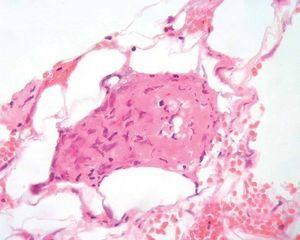

Se delimitaron las lesiones y se realizó desbridamiento de las áreas necróticas del tobillo. En el exudado obtenido al realizar la biopsia se evidenció el crecimiento de Streptococcus agalactiae (estreptoco β -hemolítico del grupo B), y se añadió clindamicina endovenosa a dosis de 600 mg cada 8 horas, según el antibiograma. El estudio histológico demostró un prominente infiltrado neutrofílico subcutáneo, con presencia de trombos y neutrófilos en vasos adyacentes y necrosis epidérmica suprayacente (figs. 3 y 4).

Fig. 4.--Los vasos de pequeño y mediano calibre presentan necrosis de la pared vascular con escaso componente neutrofílico (H&E, x 400).